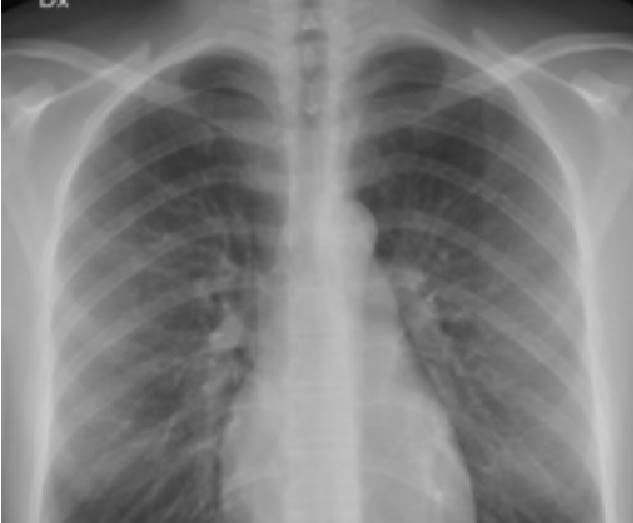

Una vez el doctor revisa los síntomas del paciente (tos seca, disnea, etc.) este pide una radiografía (figura 5), una espirometría (figura 10), y en algunos casos un examen llamado “gases arteriales” (figura 13) para determinar las causas. Si en las radiografías se empiezan a ver unas “líneas” (figura 6), se inician las sospechas, por lo que es fundamental solicitar una tomografía o tac de tórax (figura 7). Respectivamente la espirometría muestra la capacidad del pulmón espirando e inspirando (figura 10) en un paciente con fibrosis del pulmón, las capacidades del pulmón son bajas (figura 12) considerando que este está cicatrizado y no se puede expandir de la misma manera, a esto se le denomina patrón restrictivo; en cuanto a los gases arteriales (examen en el que se ve como está el oxígeno), cuando un paciente tiene fibrosis del pulmón el examen muestra como el oxígeno empieza a presentar niveles más bajos de lo normal (figura 12). Finalmente se puede complementar con un examen llamado “caminata de seis minutos”, en este el paciente se pone a caminar en una pista durante seis minutos con un oxímetro de pulso, acá los pacientes suelen presentar las principales características de la fibrosis pulmonar y este se empieza a ahogar o hace disnea, cuando presenta estos síntomas, la oxigenación, la cual se mide con un examen que se llama saturación (con el oxímetro de pulso) muestra que se empieza a bajar la saturación. Si el paciente presenta factores de riesgo, como trabajar en minas o tener enfermedades autoinmunes, se cruza esa información y ahí es donde se llega la sospecha inicial de fibrosis pulmonar.

Figura 6: Radiografía de Pulmón con Fibrosis

Radiografía de Tórax (Fibrosis Pulmonar)

La segunda es una radiografía de tórax donde empiezan a salir las “líneas” blancas (circuladas en rojo). Estas líneas son llamadas intersticio por eso la fibrosis pulmonar está vinculada a las enfermedades intersticiales. (figura 6)